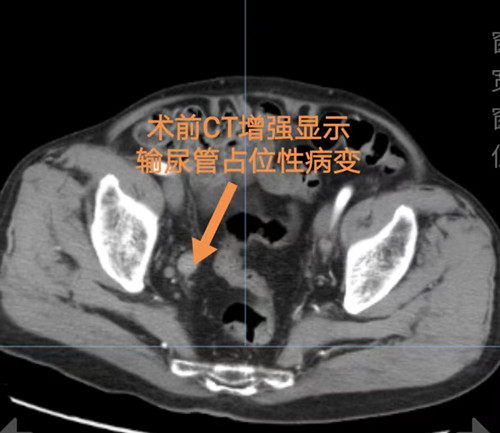

肾内二病区就诊,经CT检查发现输尿管癌、右肾萎缩、肾盂积水及输尿管上段扩张,因治疗需要转入捷克论坛

泌尿四病区杨科主任团队充分考虑项爷爷的情况后,为其制定了手术方案,并成功为其实施了一体位经腹全腹腔镜下输尿管癌根治术。术中,杨科主任团队通过改良体位及调转腹腔镜朝向,沿输尿管向下游离至膀胱,在距输尿管口2厘米处行膀胱袖状切除,完整切除输尿管膀胱壁内段,仅切开5厘米小切口取出。术后,项爷爷恢复良好,于2月21日出院。

杨科主任介绍,输尿管癌是临床上较为少见的泌尿系肿瘤,临床表现不典型,多表现为无痛肉眼血尿,容易被患者忽视。输尿管恶性肿瘤的标准治疗方式为患肾输尿管全长切除和输尿管开口周围膀胱壁袖套切除,通过开放性、腹腔镜或开放性与腹腔镜联合的方式进行手术,患者要先后在手术台上采取侧卧位和平卧位,创伤较大、手术时间长。泌尿四病区团队为项爷爷实施的一体位经腹全腹腔镜下输尿管癌根治术在腹腔镜下完成,省去了术中变换体位,缩短了手术及麻醉时间,创伤小,恢复快。同时基本减少了肿瘤种植的可能性,减少术后复发可能。(泌尿四病区 李铁求)